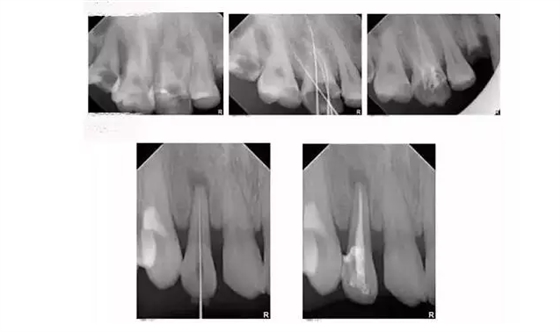

為什么根管治療需要拍多張片?

根管治療時(shí),拍牙片是必要的,并且至少要保證3張牙片。

第一張:在治療前,幫助醫(yī)生了解牙根的基本情況,如根管預(yù)備是否到位等,并制定計(jì)劃。

第二張:在治療中,幫助醫(yī)生了解治療情況,如根管預(yù)備是否到位等,并指定下一步的計(jì)劃。

第三張:在治療結(jié)束后,幫助判定根管填充質(zhì)量,發(fā)現(xiàn)問(wèn)題及時(shí)補(bǔ)救。